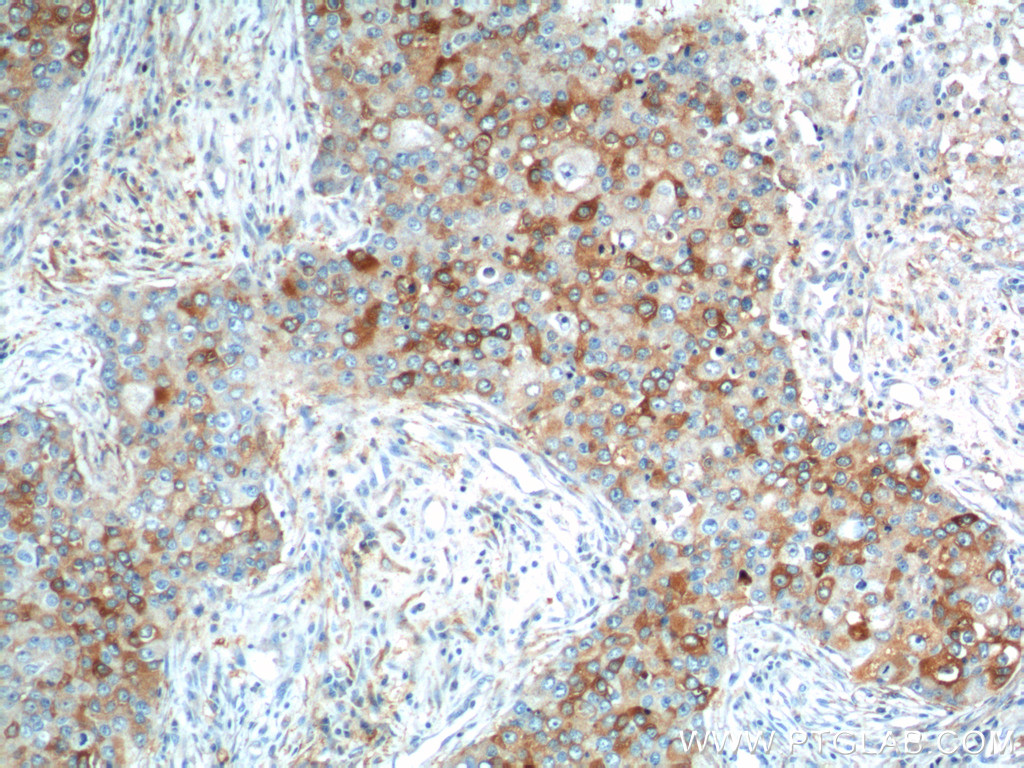

| Positive IHC detected in | human breast cancer tissue, human brain tissue, human gliomas tissue, human liver cancer tissue, human ovary tumor tissue Note: suggested antigen retrieval with TE buffer pH 9.0; (*) Alternatively, antigen retrieval may be performed with citrate buffer pH 6.0 |

| Immunohistochemistry (IHC) | IHC : 1:50-1:500 |

11059-1-AP targets IL-13RA2 in WB, IHC, IF, IP, ELISA applications and shows reactivity with human samples.

IL13RA2, also named as IL13R and CD213a2, belongs to the type I cytokine receptor family. It binds as a monomer with high affinity to interleukin-13 (IL13), but not to interleukin-4 (IL4). IL13RA2 lacks the cytoplasmic domain for signaling, indicating that it acts as a decoy receptor. IL13RA2 gene polymorphisms have been associated with systemic sclerosis (PMID: 16981293). Overexpression of IL13RA2 gene has been reported in several types of cancer, including melanoma, lung cancer, and brain tumor, which makes it a potential immunotherapeutic target (PMID: 19895199; 24970476; 24021875).